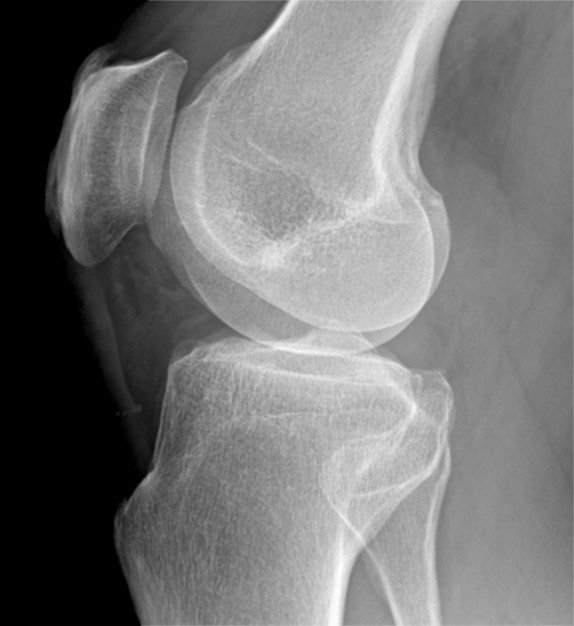

Examinarea prin computer tomograf a genunchiului este indicată în traumatismele cu suspiciune de fractură, dar și în alte patologii atunci când examinarea prin rezonanță magnetică nu este disponibilă sau este contraindicată.

Examinarea prin computer tomograf durează câteva zeci de secunde, în funcție de rapiditatea computer tomografului. Poziția pacientului este similară cu cea de la rezonanță magnetică.

Achiziția imaginilor se face după protocoale dedicate articulațiilor mari, în care avem nevoie de o scanare fină. Scanarea trebuie să se limiteze la zona de interes pentru a nu iradia inutil pacientul, dar fără să scăpăm din vedere faptul că fracturile, mai ales cele spiroide, pot fi foarte lungi și trebuie să avem în imagine tot traiectul.

După achiziția inițială a imaginilor, pacientul poate să părăsească computer tomograful, urmând partea mai complicată de postprocesare. În această etapă se fac reformatări în toate planurile, atât coronal, cât și sagital și se analizeză imaginile atât în fereastra dedicată de os, cât și în fererastra dedicată țesutului moale. Se realizează reconstrucții 3D ale regiunii scanate, pentru o mai bună exemplificare a regiunii. Aceste proceduri postprocesare sunt deosebit de laborioase și de obicei sunt realizate de medicul radiolog sau de un operator foarte bine pregătit.